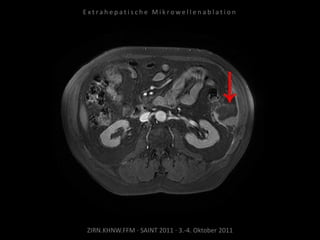

Bildgebung vor MWA:

CT vom 14.07.2010

Metastase lateral der linken Niere

nahe Colon descendens progredient.

Situation:

Metastasierung über längeren Zeitraum

lokal begrenzt,

1 Metastase progredient.

Organnahe Lage in unmittelbarer

Nachbarschaft zur linken Niere bzw. zum

Colon descendens.